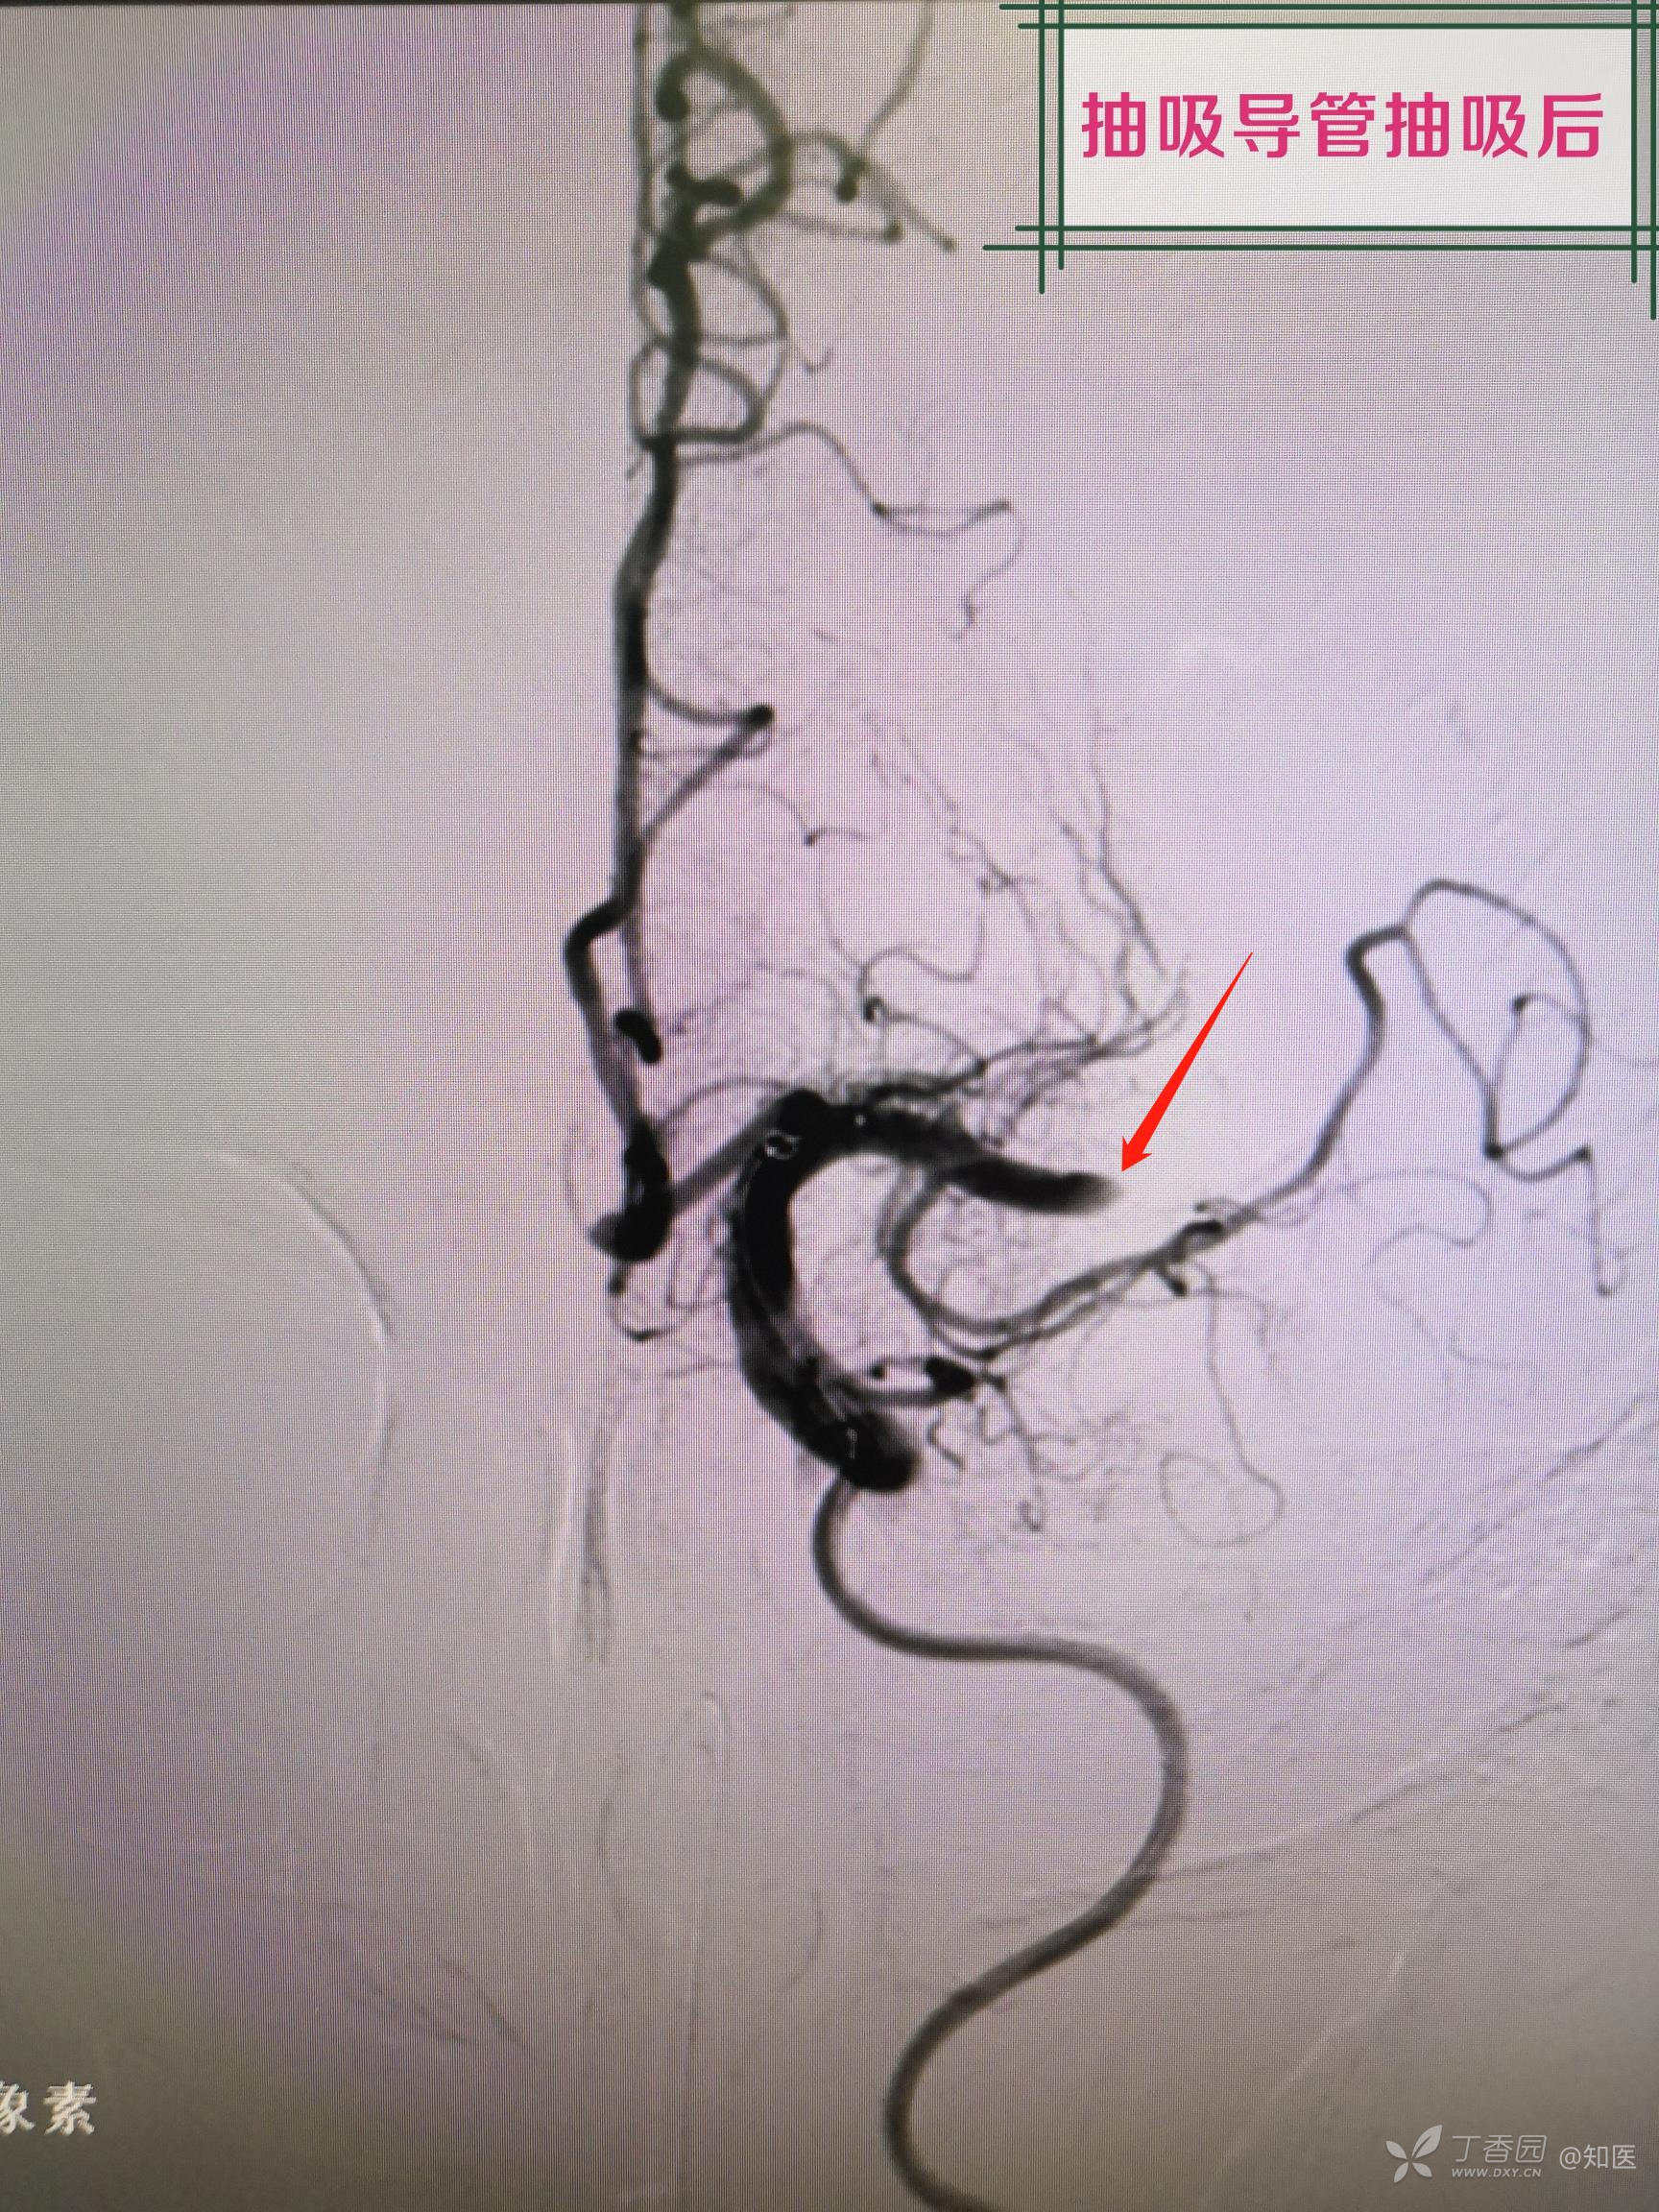

简述手术过程:采用同轴技术将8FGuiding置于左侧颈内动脉颈段,造影显示左侧大脑中动脉M2段局部白色血栓样病变,微导丝及微导管导引下将6F中间导管置于左侧大脑中接近白色血栓样病变,经中间导管尾端负压抽吸未见回血,持续负压吸引下将中间导管回撤至颈内动脉末端后,回抽未见血栓,再次造影显示左侧大脑中动脉完全闭塞,主手术者考虑血管内膜受损所致夹层闭塞。更换微导丝配合微导管通过闭塞段,将微导管置于闭塞远端,撤出微导丝,经微导管造影确认真腔,交换长导丝将1.5mm-15mm球囊置于狭窄段(局部白色血栓样病变段),给予8ATM扩张,造影见局部白色血栓样病变段90%狭窄,远端血流恢复,经导管给予欣维宁10ml,观察15min,再次造影见残余狭窄仍有90%,贴覆3.0mm-15mm支架于狭窄段,再次造影见残余狭窄约80%,支架覆盖部位造影显示仍有白色类似血栓样病变。由于多次使用及更换微导丝探测,微导丝进入左侧大脑中远端分支,远端分支血管周围可见造影剂外渗,未来得及中和肝素,患者呕吐咖啡色样胃内容物,血氧饱和度下降,心率增快,生命体征不平稳,向家属告知手术结果后终止手术。

疑问:1.如果是血栓,为何抽吸导管接近抽吸后未见血栓?

2.为何中间导管抽吸后再次造影显示左侧大脑中动脉完全闭塞?